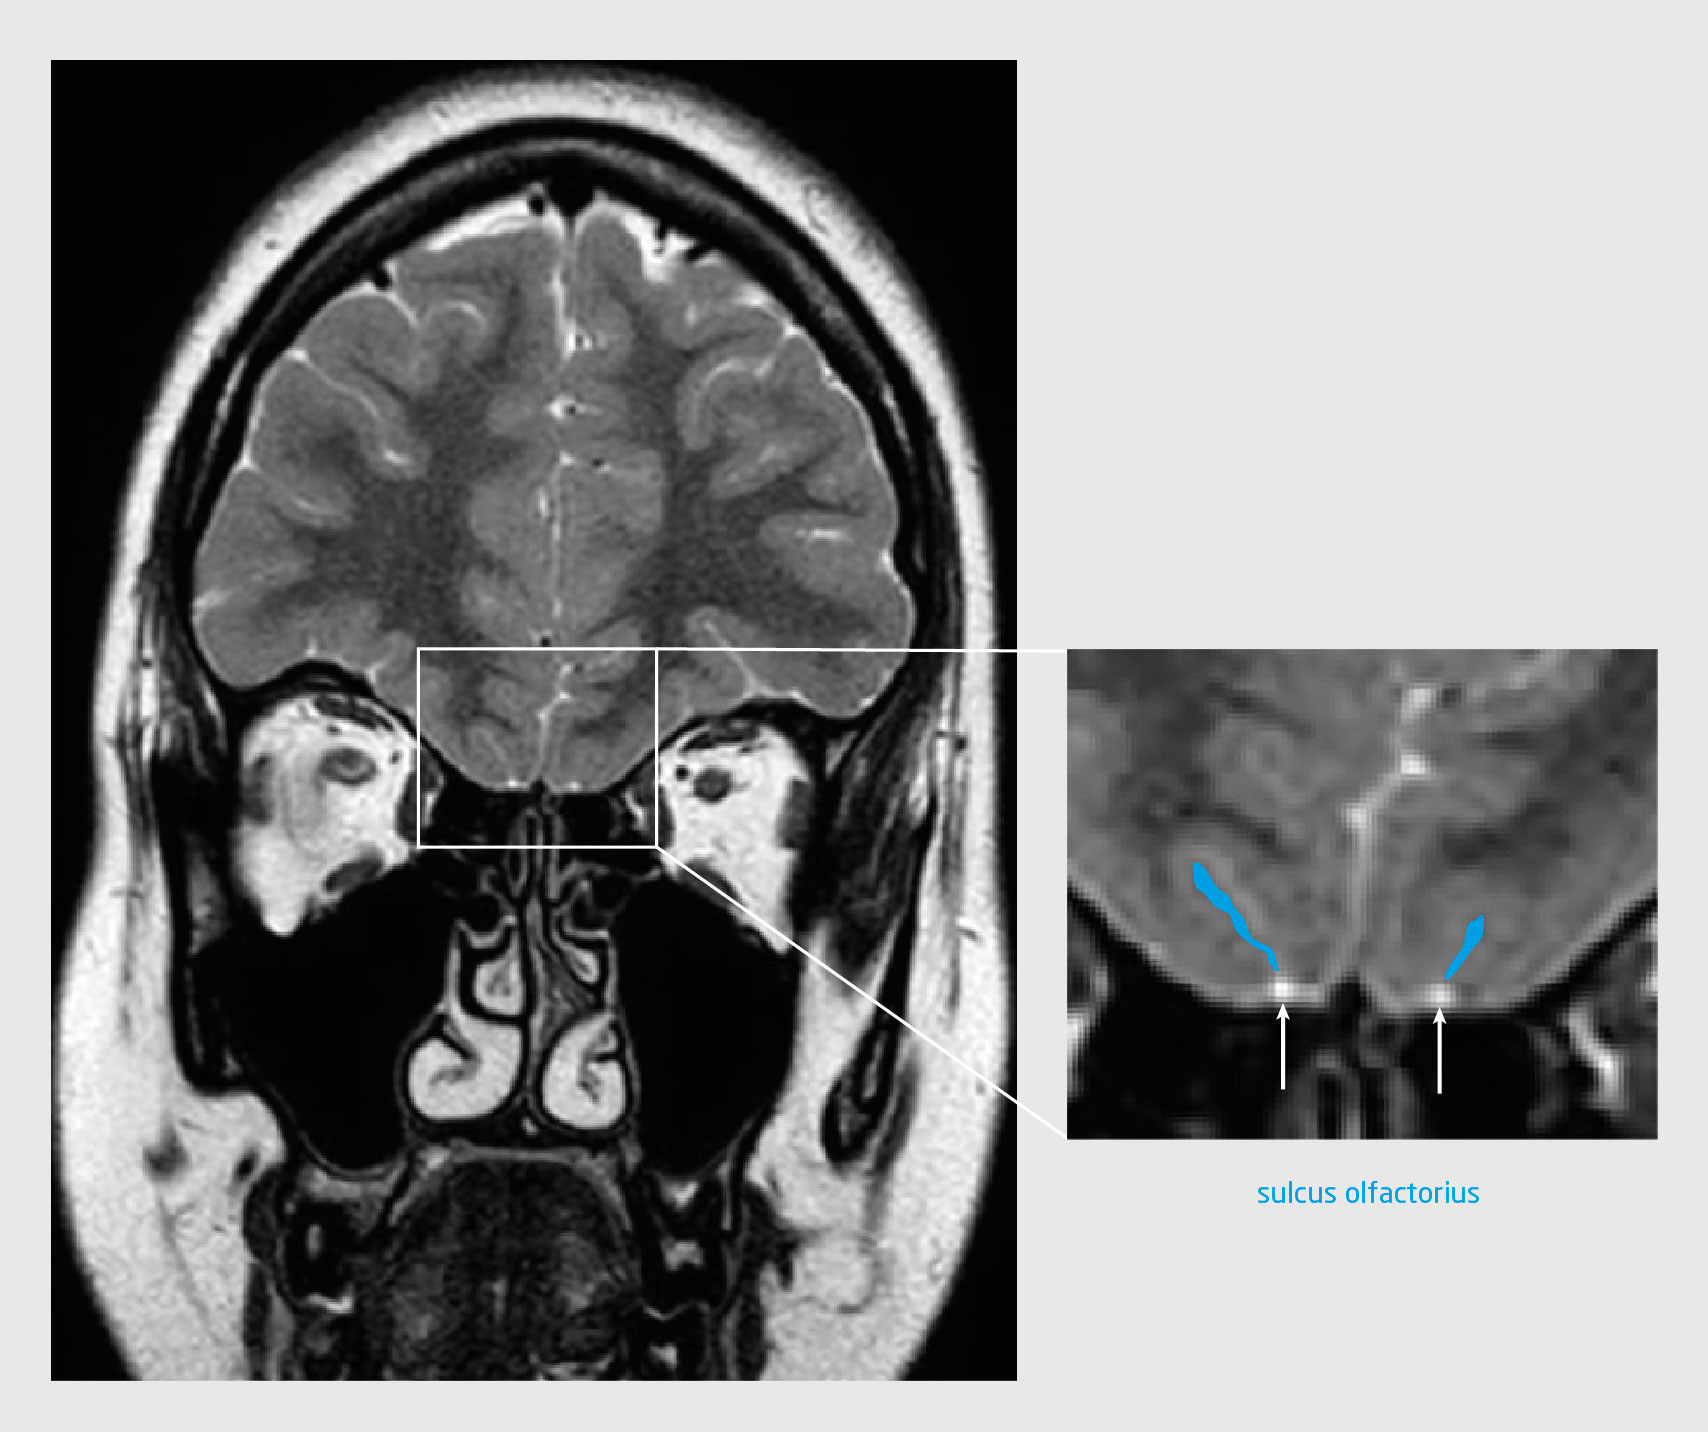

Patiënt A, een 19-jarige vrouw, kwam op de polikliniek KNO omdat ze van jongs af aan geen reukvermogen had. Zij was onderdeel van een eeneiige tweeling; haar zus kon wel goed ruiken. De reuktest liet een score zien die paste bij een afwezig reukvermogen (anosmie). Het KNO-onderzoek inclusief nasendoscopie liet een vrije middelste neusgang en reukspleet zien. We vermoedden een congenitale anosmie en verrichtten een MRI-scan. Deze liet beiderzijds een volledig afwezige bulbus olfactorius zien. De sulcus olfactorius was wel aanwezig (figuur 1).

Figuur 1 | De hersenen van de patiënte met congenitale anosmie

T2-gewogen turbospinecho-MRI van de hersenen van patiënt A (coronale coupe). Ter hoogte van de voorste schedelbasis is beiderzijds de bulbus olfactorius afwezig (witte pijl). De sulcus olfactorius (blauwe lijn) oogt beiderzijds normaal. Bij patiënten met het syndroom van Kallmann kan deze soms ook afwijkend of zelfs afwezig zijn.